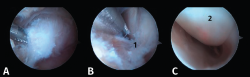

Figura 4. A: imagen artroscópica que muestra el ligamento peroneo-astragalino posterior (LPAP) (1); B: resección del LPAP con un sinoviotomo orientado medialmente contra la cara lateral del proceso posterolateral del astrágalo (PPA) (2); C: cara lateral del PPA después de la resección del LPAP.

- Primer paso: retirar el LPAP, completamente en caso de PPAH y parcialmente en caso de OT. La resección del tejido ligamentoso se realiza apoyando la ventana del sinoviotomo contra el lateral del PPA (Figuras 4 A, B y C).